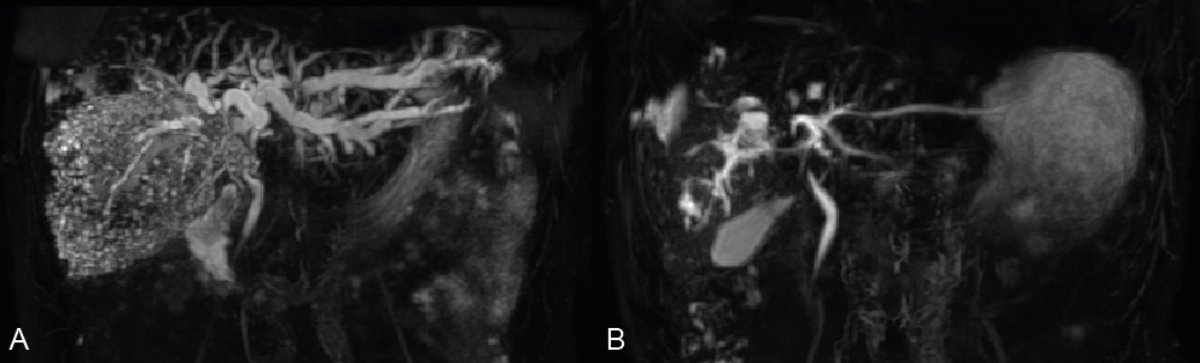

Patients in group B showed a slower resolution of hyperbilirubinaemia, with a calculated bilirubin half-life of 3.0 weeks ≈ 21 days (figure 2). A significant regression of intrahepatic bile duct dilation could be observed on magnetic resonance cholangiopancreatography (MRCP), when performed (figure 3). In this group, only one early biliary complication was reported (table 3). This patient had cholangitis that resolved with antibiotic therapy alone (table 3). Only 6/17 patients (35%) were hospitalised at treatment initiation and the median duration of the hospital stay was significantly shorter when compared to group B (table 3). Two patients in this group received surgical resection of the alveolar echinococcosis lesion after resolution of hyperbilirubinaemia after four and five months of follow-up (table 3).

Figure 3Representative magnetic resonance cholangiopancreatography (MRCP) of a patient treated with benzimidazole therapy alone (group B). The left MRCP image indicates the status before benzimidazole initiation (A) while the right panel illustrates the biliary tract following six months of therapy (B). Note the striking decrease in bile duct dilation. Bilirubin levels were 227 µmol/l at initial presentation and had completely resolved (10 µmol/l) by six months.